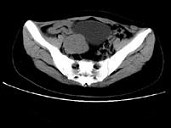

- 单项选择题女,24岁, 近日尿频明显,CT检查如图所示, 最可能的诊断是 ( )

A、膀胱癌

B、子宫肌瘤

C、卵巢癌

D、盆腔纤维瘤

E、卵巢囊肿